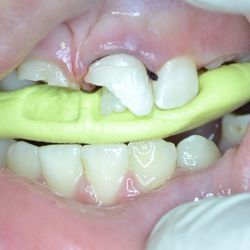

Η νεαρή αυτή ασθενής προσήλθε στο ιατρείο παραπονούμενη για την εμφάνιση των τεσσάρων άνω τομέων της.

Τα δόντια είχαν με την πάροδο των ετών σπάσει στην κοπτική τους επιφάνεια και το φαινόμενο αυτό επιδεινώνονταν σταδιακά με απώλεια όλο και περισσότερης οδοντικής ουσίας.

Αποφασίστηκε να αποκατασταθεί η δομική ακεραιότητα των δοντιών αυτών με χρήση σύνθετης ρητίνης νανουβριδικής τεχνολογίας (Herculite XVR Ultra/Kerr).

Η αποκατάσταση τους έγινε σε ένα ραντεβού και το αισθητικό αποτέλεσμα ικανοποίησε στο ακέραιο τις προσδοκίες της ασθενούς μας.